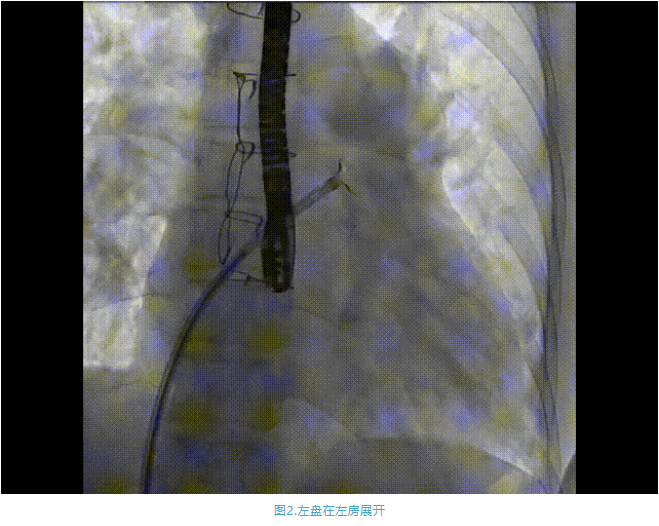

術(shù)中首先在局麻下穿刺股動脈、股靜脈,完成心導(dǎo)管檢查評估后轉(zhuǎn)為全麻,在食道超聲引導(dǎo)下穿刺房間隔,穿刺成功后將加硬導(dǎo)絲送入左上肺靜脈建立軌道,根據(jù)患者病情行球囊預(yù)擴(kuò)張后植入6mm孔徑房間隔造孔支架,經(jīng)透視及食道超聲評估支架左右盤展開良好,夾持于房間隔兩側(cè),固定穩(wěn)定、位置良好,食道彩超顯示房水平右向左為主分流,分流孔直徑符合預(yù)期大小,心導(dǎo)管檢查評估達(dá)到預(yù)期效果,釋放造孔支架。術(shù)后12h患者下床活動,恢復(fù)順利,擬于近日完善術(shù)后評估后出院。